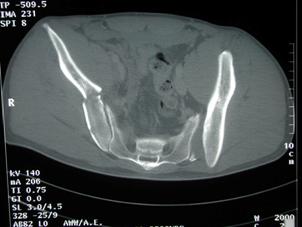

Fractura Malgaigne Fractura Malgaigne. Imagine CT

Fractura de

aripa iliaca stanga Fractura de aripa iliaca

stanga

Disjunctie sacro-iliaca stanga Disjunctie

sacro-iliaca stanga Aspect CT